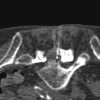

Lumbar epidural injections are typically performed blindly or with fluoroscopic guidance. CT fluoroscopy (CTF) can be used to guide needle placement precisely and rapidly, allowing visualization of the optimal needle path and identifying potential problems such as severe stenosis and synovial cysts before needle insertion. Operator and patient radiation dose is minimal when using the intermittent CTF technique and low mAs. By using this technique, just more than 2000 epidural steroid injections have been performed with no major complications. CTF is a useful guidance tool when performing lumbar epidural injections.